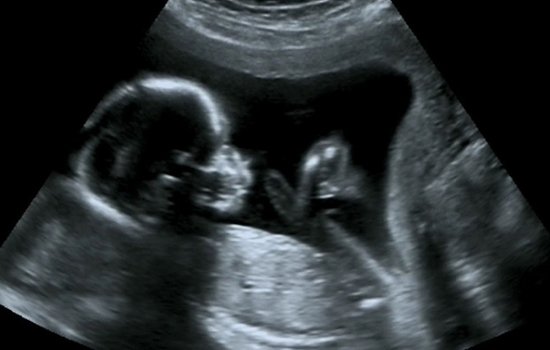

孕检B超图说明

胎囊

胎囊只有在怀孕早期才能够看到,怀孕一个月时胎囊直径大约二厘米,到怀孕两个半月时胎囊直径约为五厘米。胎囊在了宫的宫底、前壁、后壁、上壁、中部都属正常。正常情况下B超所视的胎囊形状清晰,呈圆形或椭圆形。